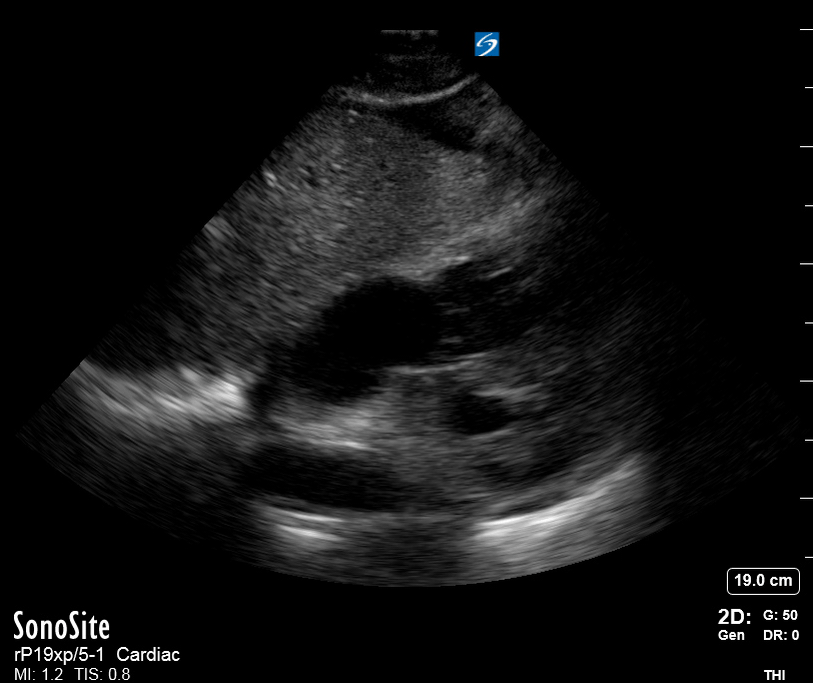

THE VIEWS

The PLAX view is versatile and allows the recognition of multiple landmarks, making it good for visual estimation of LV contractility. It is essential to optimize the view ensuring a true sagittal long axis, as being oblique to the LV chamber may underestimate its size and overestimate its emptying. The PSAX view at the level of the papillary muscles reveals the entire muscular circumference and concentric squeeze of the LV. It is useful to estimate both global function and focal wall motion abnormalities. The A4C view, although technically challenging, provides good insight into the global myocardial function and chamber size.

LV CONTRACTILITY

Qualitative assessment of the LV and visual estimation of Ejection Fraction is based on three parameters:

Endocardial excursion.

Myocardial thickening.

Movement of the anterior leaflet of the mitral valve.

A qualitative assessment is typically categorised as:

Normal (LVEF 50-65%)

Moderately Depressed (LVEF 30-50%)

Severely Depressed (LVEF < 30%)

Hyperdynamic (LVEF > 65%)

SIGNIFICANTLY IMPAIRED / DILATED LV

A severely depressed LV contractility, particularly when paired with a plethoric IVC or lung B-lines, indicates systolic heart failure. Chronically raised afterload can lead to severe dilation of the LV.